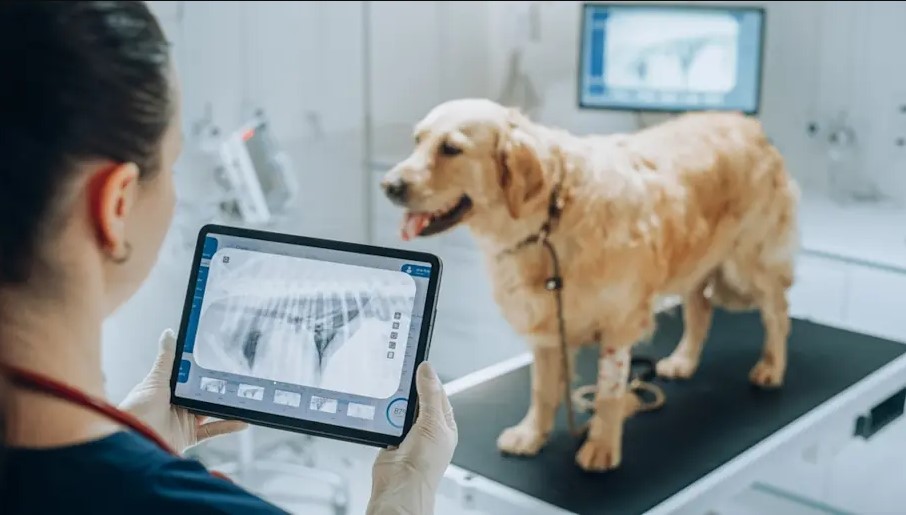

Un Sistema diseñado para la gestión integral en Radiología Veterinaria.

Un Sistema diseñado para la gestión integral en Radiología Veterinaria.

Además de las funcionalidades de Radiología, hemos incorporado recursos en Medcloud RIS, especialmente diseñados para Medicina Veterinaria, como la selección de razas y especies.

Un Sistema diseñado para la gestión integral en Radiología Veterinaria.